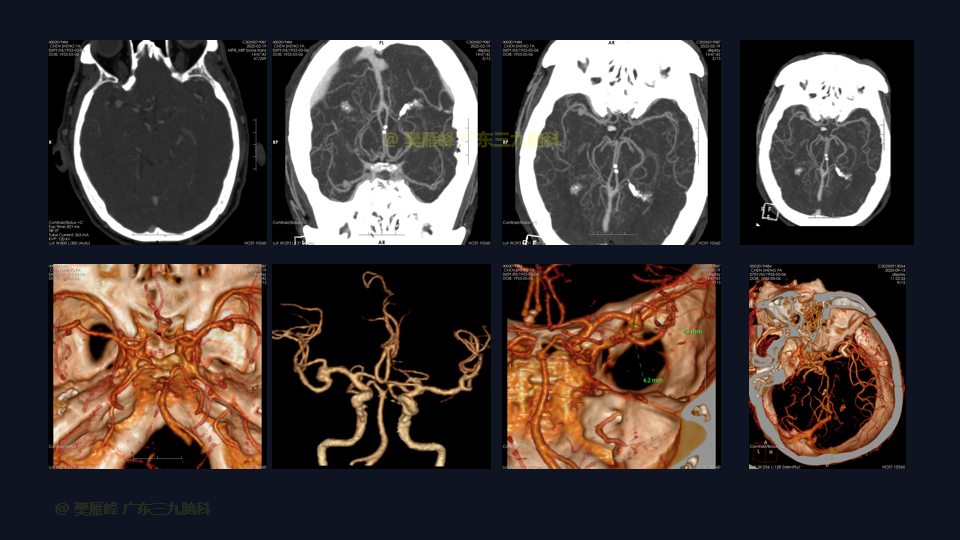

我们介绍一名69岁男性病例,他因反复头晕2个月发现的一个大型、宽颈、未破裂的MCA复杂性动脉瘤。由于动脉瘤的形态、位置和破裂风险,选择了显微外科夹闭。进行了右侧翼点入路,患者外侧裂较难分离。手术视频重点介绍了关键步骤,如分离复杂外侧裂、去除额叶粘连、实现近端和远端控制,以及在临时阻断下夹闭。夹闭后血管造影确认分岔重建良好,动脉瘤完全消失,MCA循环得以保留。术后患者神经功能完好,于术后第 10天出院。本病例强调了针对复杂MCA动脉瘤量身选择适当的动脉瘤夹重建的重要性,采用精细的侧裂分离技术和细致的动脉瘤颈剥离技术。显微外科夹闭仍是处理大型复杂MCA动脉瘤的首选方法,尽管存在固有风险,但具有高闭塞率和实用性。

在这段手术视频中,展示了一名69岁男性的病例,他因反复头晕2个月发现的大脑中动脉动脉瘤